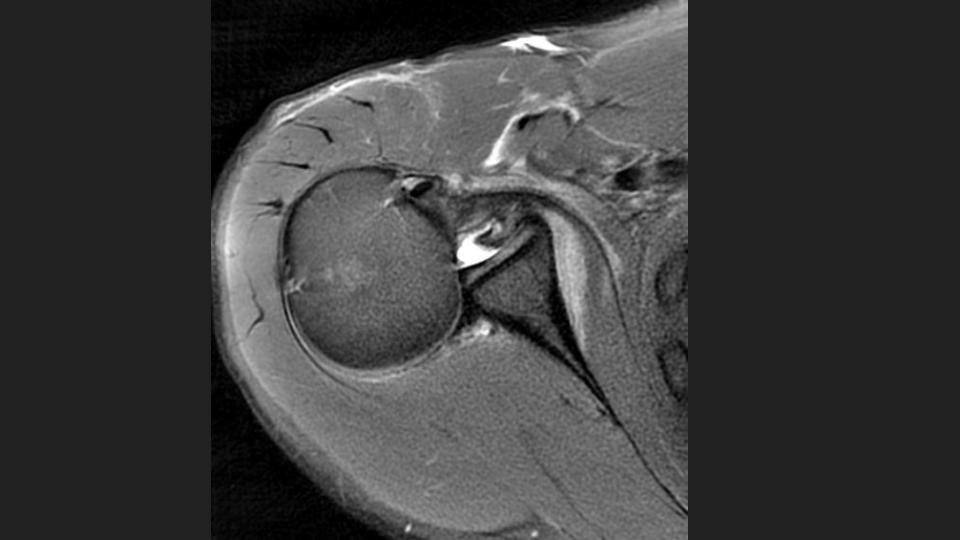

36M with chronic pain and limited motion 3 years after work related injury

My colleague had to share this with me after a failed attempt at arthrography. He puts the shoulder in Grashey, but it doesnt really look like Grashey. No matter what, he couldnt get in and converted it to a routine MRI. The first set of Cor images look so nice....or do they? The crazy thing is that the injury was 3 years ago. Not all workers comp is bogus. I was taught the posterior shoulder dislocation locks the shoulder in internal rotation, but based on the axial image, it is not. 1) Why is that? 2) I think thats partly why the scout image for the arthrogram was so misleading.

dislocation ( RID4770 )